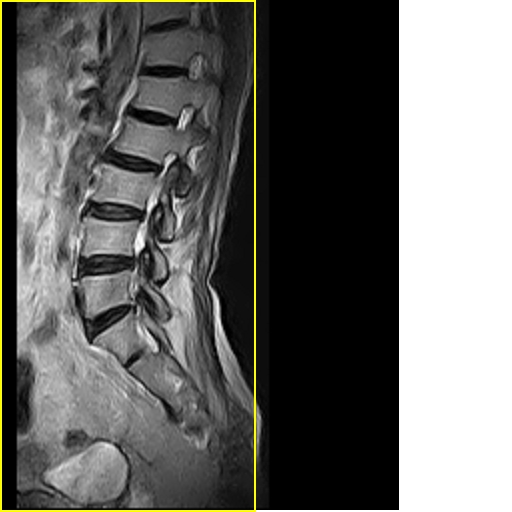

标题: MRI0859:[原创]腰椎,男,78岁,右下肢跛行两月 [打印本页]

男,78岁,右下肢跛行两月.

右侧黄韧带肥厚或钙化,压迫马尾神经所致。必要时行ct扫描。

腰间盘膨出、黄韧带肥厚、可疑先天性腰椎管狭窄。

退行性骨关节病:增生、椎间盘变性、膨出...

退行性病变:增生、椎间盘变性、膨出[l4-5、l5-s1 椎间盘膨出]

退行性骨关节病:增生、椎间盘变性、膨出..黄韧带肥厚.

黄韧带肥厚.